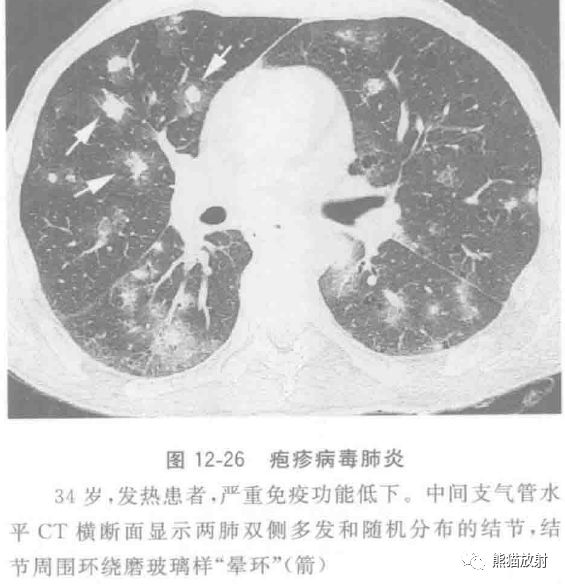

单纯疱疹病毒1型肺炎是一种可能危及生命的感染,几乎仅见于免疫功能低下和(或)机械通气的患者,通常是多种微生物感染中的一部分。

CT表现包括斑片状肺叶、段或亚段性的实变影和磨玻璃状致密影;伴小叶中央结节及树芽征,后者也见于单纯疱疹病毒2型感染患者;结节周围也可环绕磨玻璃样“晕环”(图12-26)。